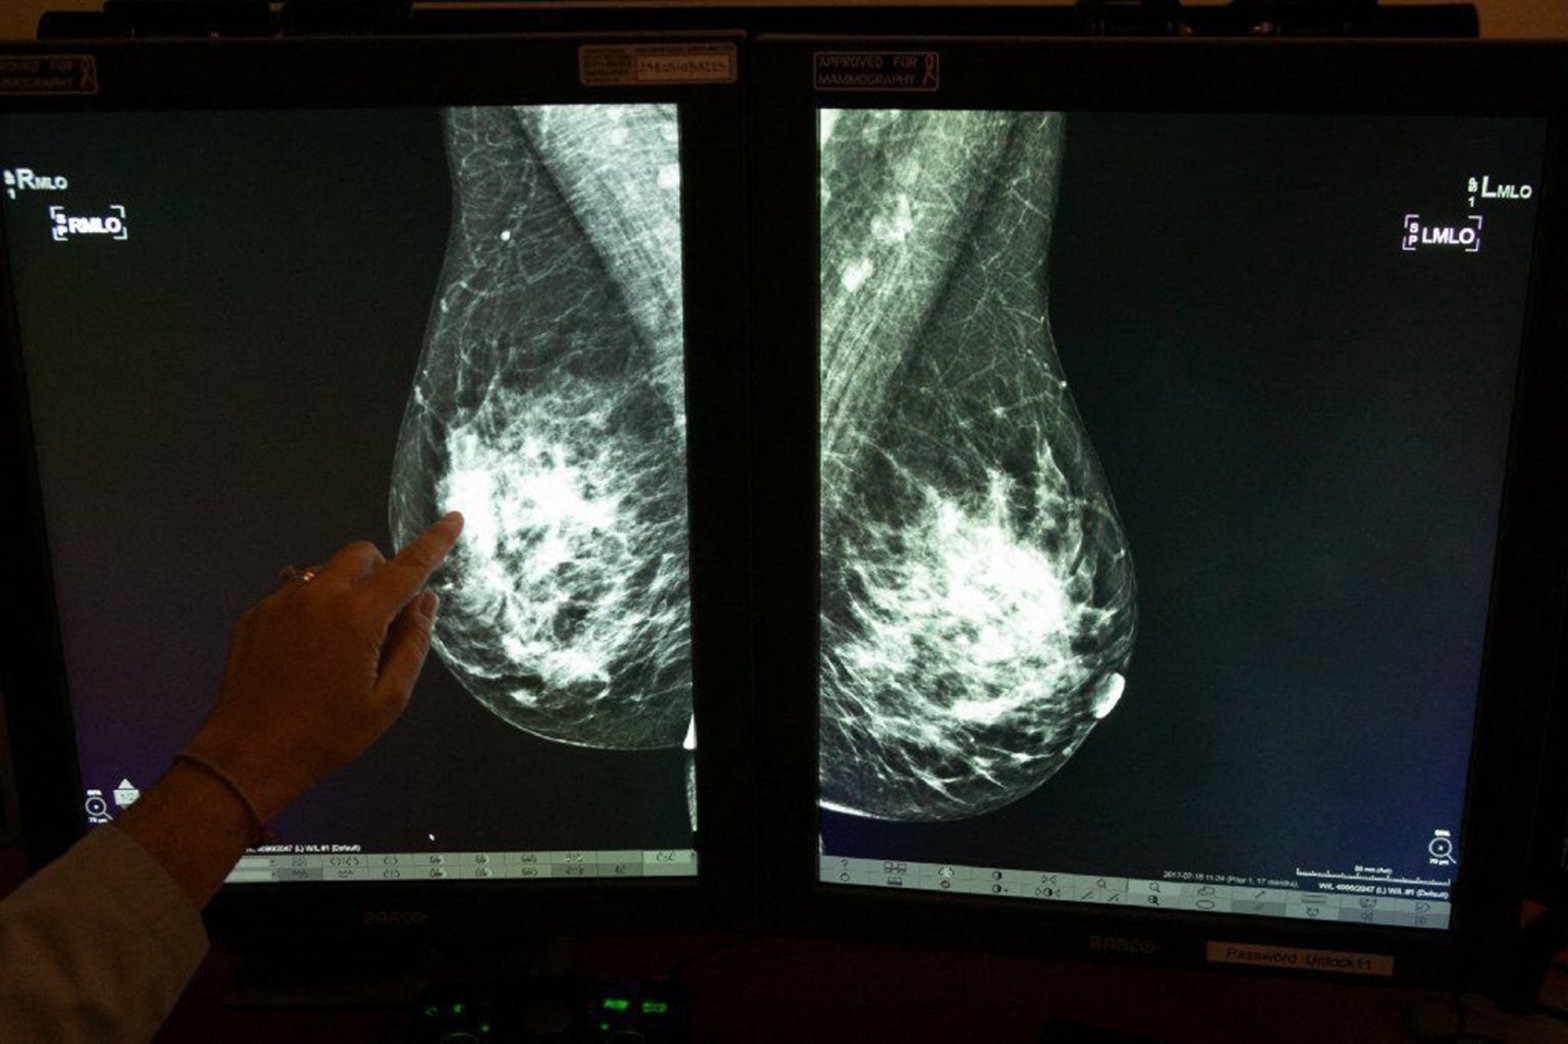

Las implicaciones de la mama densa

La mamografía se basa en una interpretación visual de los resultados de las imágenes que a menudo se confunde con el tejido mamario denso. El tejido denso afecta la capacidad y precisión con las que el radiólogo puede detectar el cáncer. El tejido denso puede enmascarar la presencia de un cáncer de mama, y ​​laContinue reading “Las implicaciones de la mama densa”